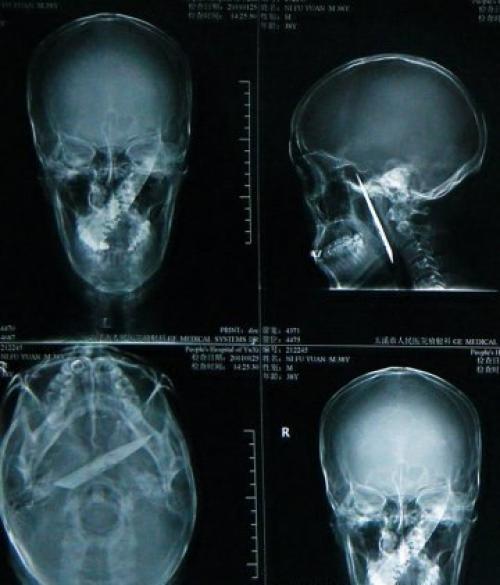

30-Летний китаец ли фуянь пришел к медикам с жалобами на сильные головные боли, неприятный запах изо рта и затрудненность дыхания. Врачи были в шоке, когда оказалось, что причиной недомогания стало 10-сантиметровое лезвие, которое находилось в черепе пациента в течении последних 4 лет.

Нож вошел под нижнюю челюсть и прошел наискосок, чудом не задев сонную артерию. Все это время больной не подозревал, что носит внутри своей головы лезвие. За эти четыре года ли регулярно колол себе болеутоляющее, чтобы справиться с чудовищными головными болями, которые регулярно мучили его.

Мужчину успешно прооперировали в народной больнице города юйси, провинция юньнань в южном Китае. Этот случай получил широкое освещение в китайских СМИ и интернете, после того, как рентгеновские снимки были опубликованы на сайте больницы.

Извлеченное из черепа 10-сантиметровое лезвие оказалось сильно корродированным. Врачи этот случай "Настоящим Чудом называют". Поражает тот факт, что лезвие прошло сквозь череп, не задев жизненно важных сосудов, а также тот долгий срок, в течении которого инородное тело находилось внутри человеческого организма.